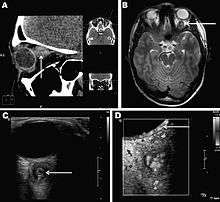

Infections in humans [2] usually manifests as a single subcutaneous nodule, which is caused by a macrofilaria that is trapped by the immune system. Subcutaneous migration of the worm may result in local swellings with changing localization. In addition, rare cases of organ manifestation have been reported, affecting the lung, male genitals, female breast, or the eye. The latter is found in particular during the migratory phase of the parasite. D. repens occurs more commonly in adults (aged 40–49 years). The only exception is in Sri Lanka, where children younger than 9 years are most likely to be infected. The youngest individual reported was aged 4 months.[3]

Final diagnosis is established by microscopic examination of the excised worm. Making a definite species diagnosis on morphologic grounds is difficult, because a large number of zoonotic Dirofilaria species have been described that share morphologic features with D. repens.